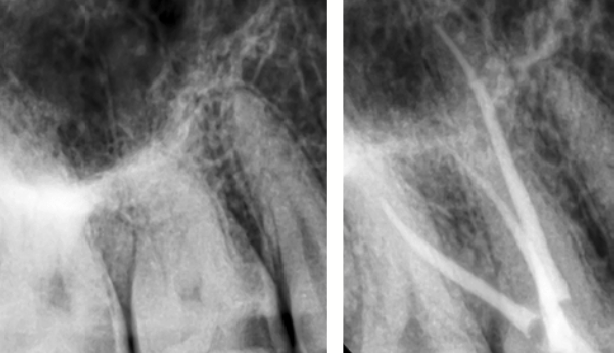

Într-adevăr, realizarea tratamentului de canal presupune, pe lângă îndepărtarea nervului, și sacrificarea unei părți din dinte, însă faptul că aceste tratamente se realizează la microscop, ne dă posibilitatea să fim extrem de conservativi cu dinții. Restaurarea adecvată a coroanei dentare după un tratament de canal scade substanțial posibilitatea de apariție a complicațiilor. Exemplu avem în acest caz de proces carios cu afectare pulpară, unde s-a îndepărtat, minim invaziv, doar țesutul afectat și s-a refăcut corespunzător peretele dentar (Fig. 4.4.2). Mai apoi a urmat tratamentul de canal. (Fig. 4.4.3)